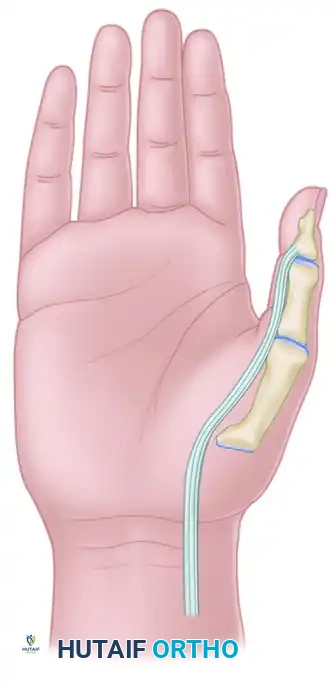

4. Subcutaneous Tunneling and Rerouting

- Create a generous subcutaneous tunnel using blunt dissection (e.g., with a curved Kelly clamp or tendon passer).

- The tunnel must originate from the forearm incision, pass along the radial aspect of the wrist and thumb, and terminate at the lateral (radial) side of the metacarpophalangeal (MCP) joint.

- Crucial Step: Ensure the tunnel is wide enough to allow unimpeded gliding of the FPL tendon. Pass the FPL tendon through this tunnel from proximal to distal.

5. Tendon Fixation and Tensioning

- Positioning for Tensioning: Hold the wrist in a neutral position (0 degrees of flexion/extension) and place the thumb in 50 degrees of palmar abduction.

- Attachment: Identify the dorsoradial aspect of the MCP joint capsule and the extensor aponeurotic hood.

- Suturing: Weave the FPL tendon into the dorsoradial capsule and extensor hood using a Pulvertaft weave or a robust side-to-side anastomosis with non-absorbable braided sutures (e.g., 3-0 or 4-0 polyester).

- Tension: The tendon must be sutured with tension to ensure that the resting posture of the hand maintains the thumb out of the palm.